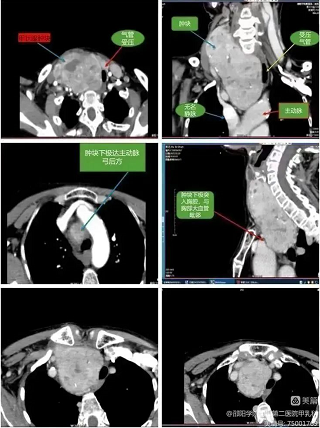

由于该患者肿块巨大,且50%位于胸骨后,肿块最下极达主动脉弓下缘,又因已行两次手术,复发肿块与周围组织粘连,可能需要行胸骨劈开切除术。

为了尽可能避免胸骨劈开给患者带来的创伤,李洲成主任带领的甲乳外科团队与胸外科、麻醉科、影像科、五官科、呼吸内科等多部门专家联合会诊讨论,制定出周密的个体化手术方案及紧急处理措施。